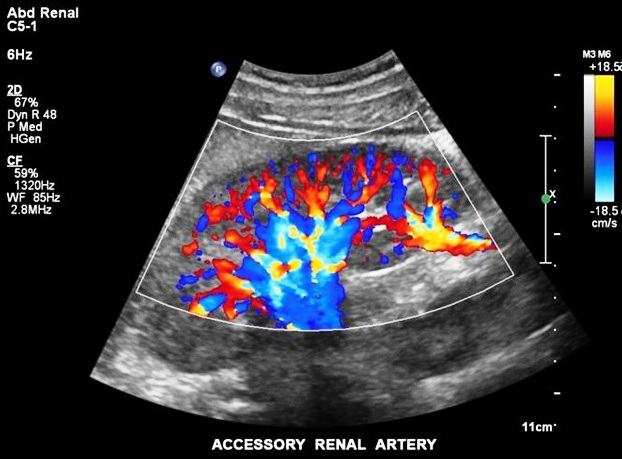

Doppler Studies

Renal Doppler

This is examination of the blood vessels supplying and draining the kidneys. A common reason for doing this test is when the patient is being investigated for hypertension. Narrowing of the artery suppying blood to the kidney may cause hypertension and this narrowing can be detected by doppler ultrasound.